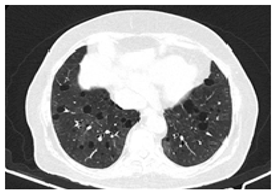

| Type of SARD-ILD | HRCT Features | Axial HRCT Images in Patients with SARD-ILD | Description of HRCT Images in Patients with SARD-ILD |

|---|---|---|---|

| IIM-ILD | NSIP or OP. | ![]() | The appearance of OP is frequently encountered in IIM-ILD patients. It is characterized by ground glass areas alternating with areas of condensation, often with a perilobular distribution. OP can overlap with NSIP, leading to exacerbations of ILD, or it may present as the initial pattern. |